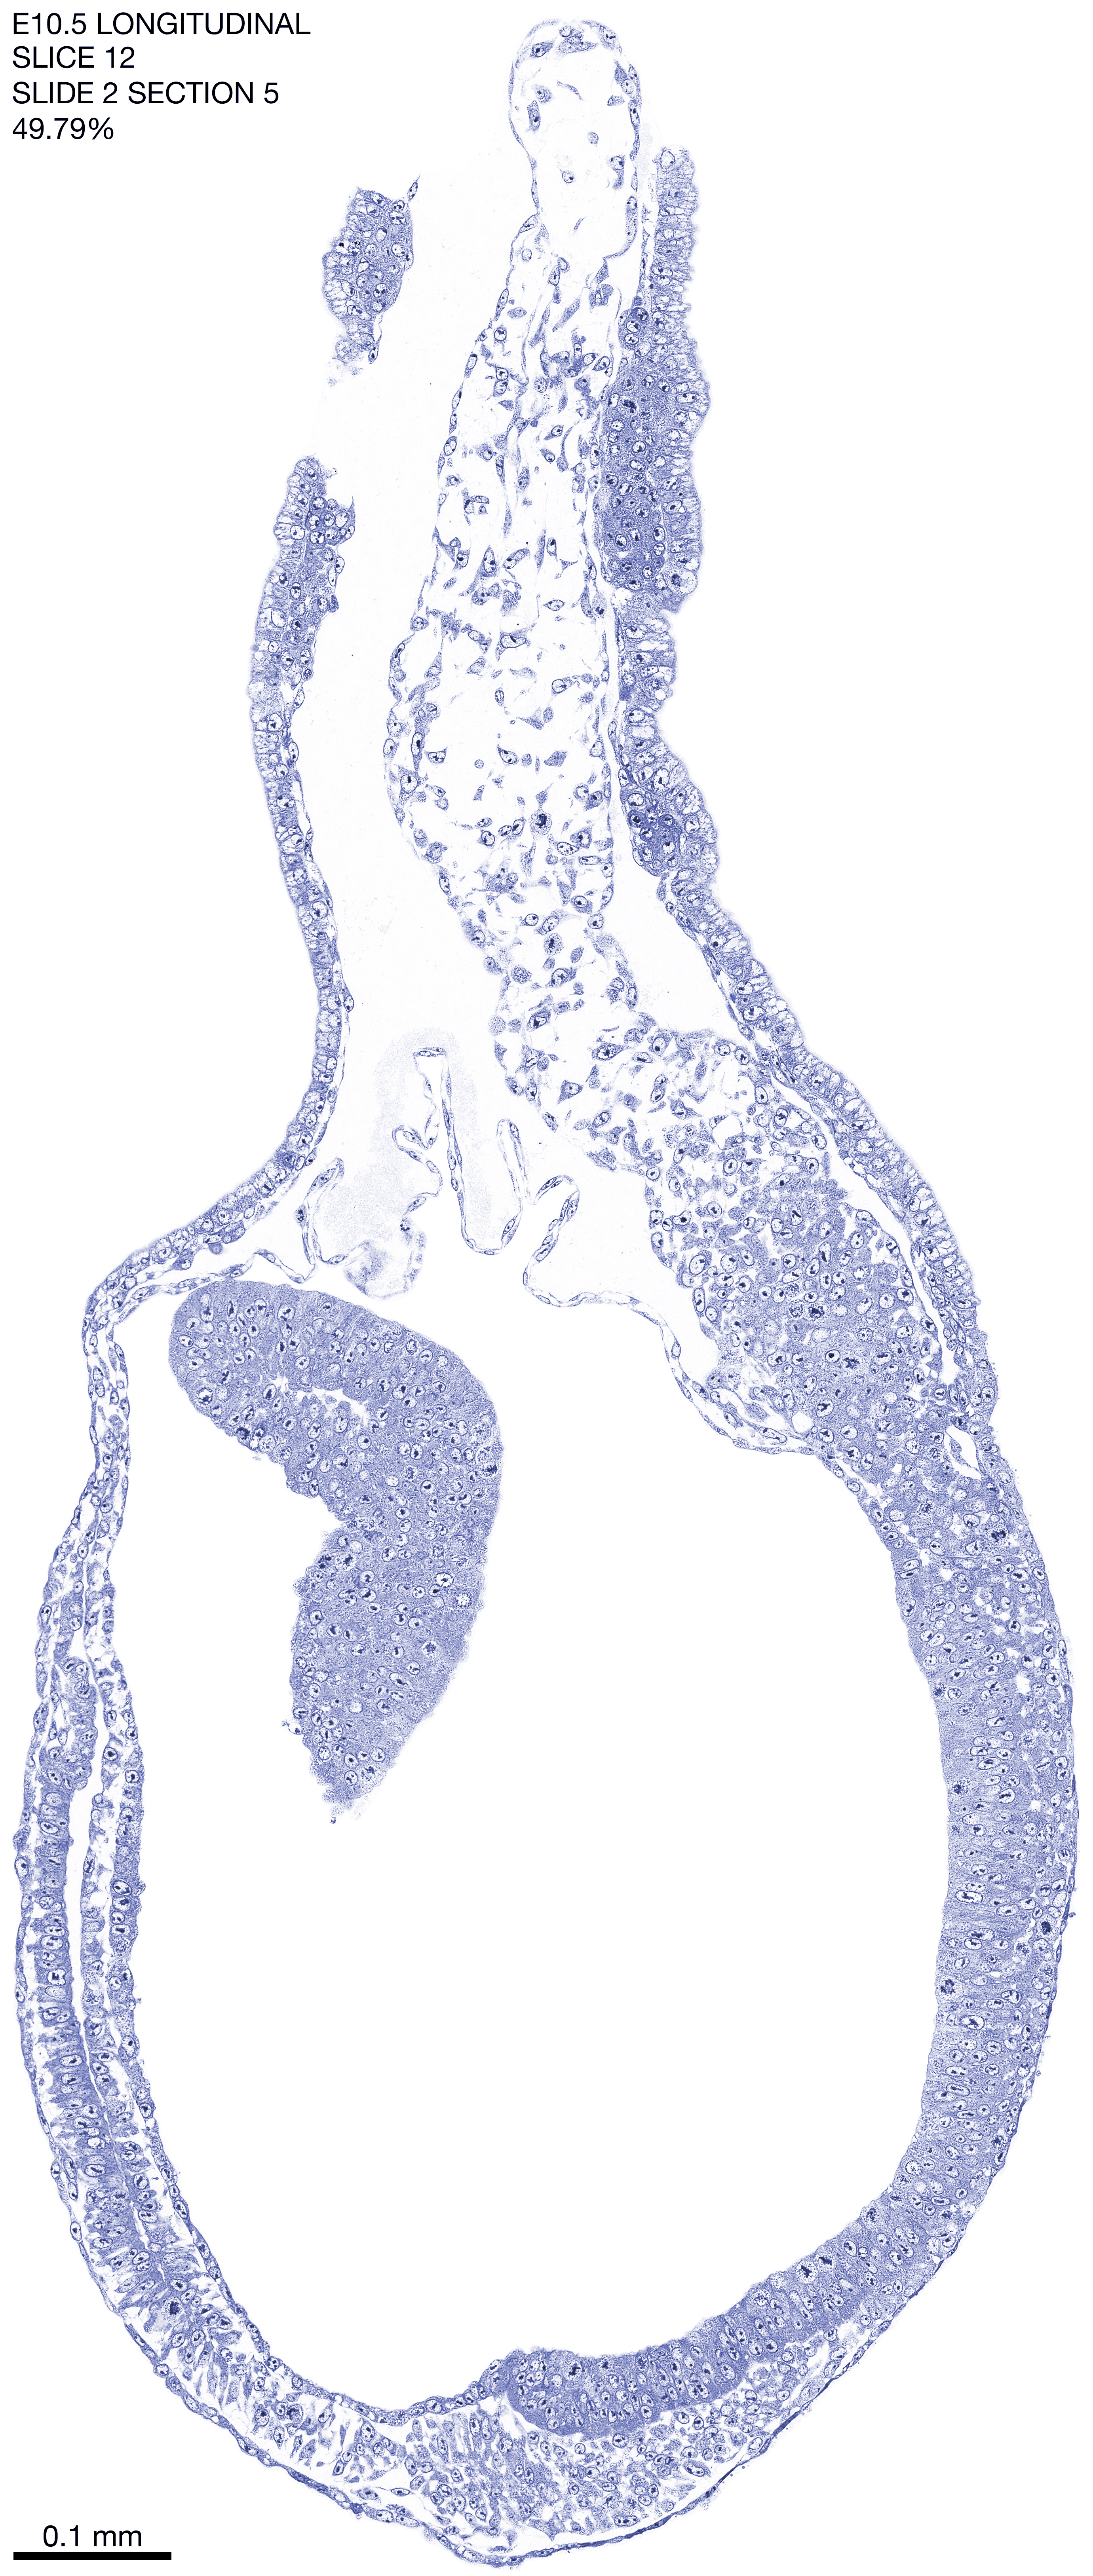

E10.5 Longitudianal Archive This page contains jpg files of ALL SLICES (each 3µm thick) that were scanned of the E10.5 longitudinally cut specimen. Download: Large | High Res Download: Large | High Res Download: Large | High Res Download: Large | High Res Download: Large | High Res Download: Large | High Res Download: Large | High Res Download: Large | High Res Download: Large | High Res Download: Large | High Res Download: Large | High Res Download: Large | High Res Download: Large | High Res Download: Large | High Res Download: Large | High Res Download: Large | High Res Download: Large | High Res Download: Large | High Res Download: Large | High Res Download: Large | High Res Download: Large | High Res Download: Large | High Res Download: Large | High Res Download: Large | High Res Download: Large | High Res Download: Large | High Res Download: Large | High Res Download: Large | High Res Download: Large | High Res Download: Large | High Res Download: Large | High Res Download: Large | High Res Download: Large | High Res Download: Large | High Res Download: Large | High Res Download: Large | High Res Download: Large | High Res Download: Large | High Res Download: Large | High Res Download: Large | High Res Download: Large | High Res Download: Large | High Res Download: Large | High Res Download: Large | High Res Download: Large | High Res Download: Large | High Res Download: Large | High Res Download: Large | High Res Download: Large | High Res Download: Large | High Res Download: Large | High Res Download: Large | High Res Download: Large | High Res Download: Large | High Res Download: Large | High Res Download: Large | High Res Download: Large | High Res Download: Large | High Res